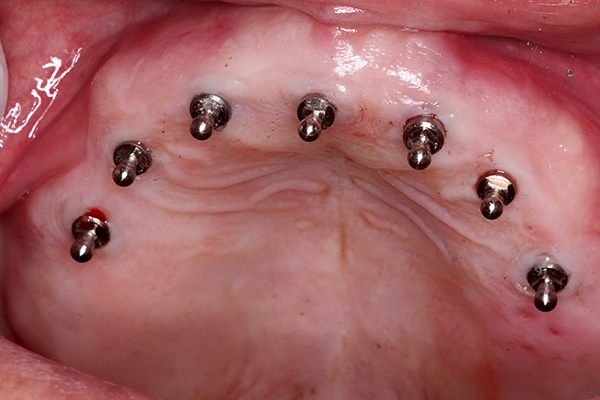

Como observado acima, os mini-implantes costumam ser usados para fixar próteses removíveis. Dependendo do tamanho da prótese, um número diferente de implantes pode ser instalado na mandíbula, na qual uma única prótese é então acoplada. Isso proporciona uma fixação rígida da prótese, sua imobilidade ao comer e conversar e, mais importante, o conforto geral do uso. Ao mesmo tempo, a prótese em si pode ser removida e instalada nos implantes várias vezes e, ao usar alguns tipos de pilares, um número ilimitado de vezes.

O número mínimo recomendado de mini-implantes sob a prótese é de 4 unidades. Se a prótese for grande e maciça, pode haver mais mini-implantes.